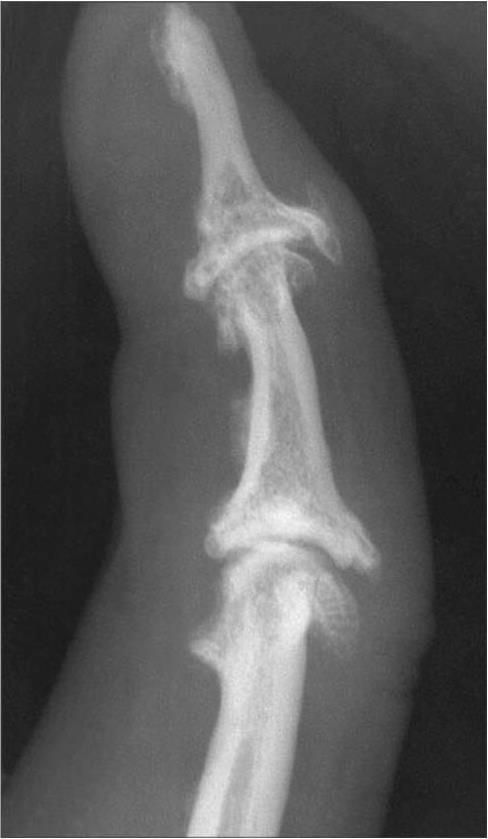

III стадия — массивные остеофиты, деформация суставных концов костей, неравномерное сужение суставной щели, выраженный субхондральный склероз. Более выраженному развитию окостеневающей хондроидной ткани по периферии способствует близость к синовиальной оболочке, васкуляризация (Астапенко М. Г., 1989). Отчетливо видны участки субхондрального склероза и мелкие эностозы. Типично неравномерное сужение суставной щели. Целостность замыкающей пластинки не нарушена, хотя контуры ее выглядят неровными. Эпифизы теряют свою равномерную трабекулярную структуру, костные трабекулы истончены, ячейки деформированы, увеличены в размерах (рис. 8).

Рис. 8. Рентгенограмма дистального и проксимального межфаланговых суставов кисти больного с III стадией первичного остеоартроза. Боковая проекция, 5-кратное увеличение

Резко выраженные остеофиты в суставных впадинах и головках на фоне множественной кистовидной перестройки. Резко выражен субхондральный склероз. Неравномерное сужение суставной щели